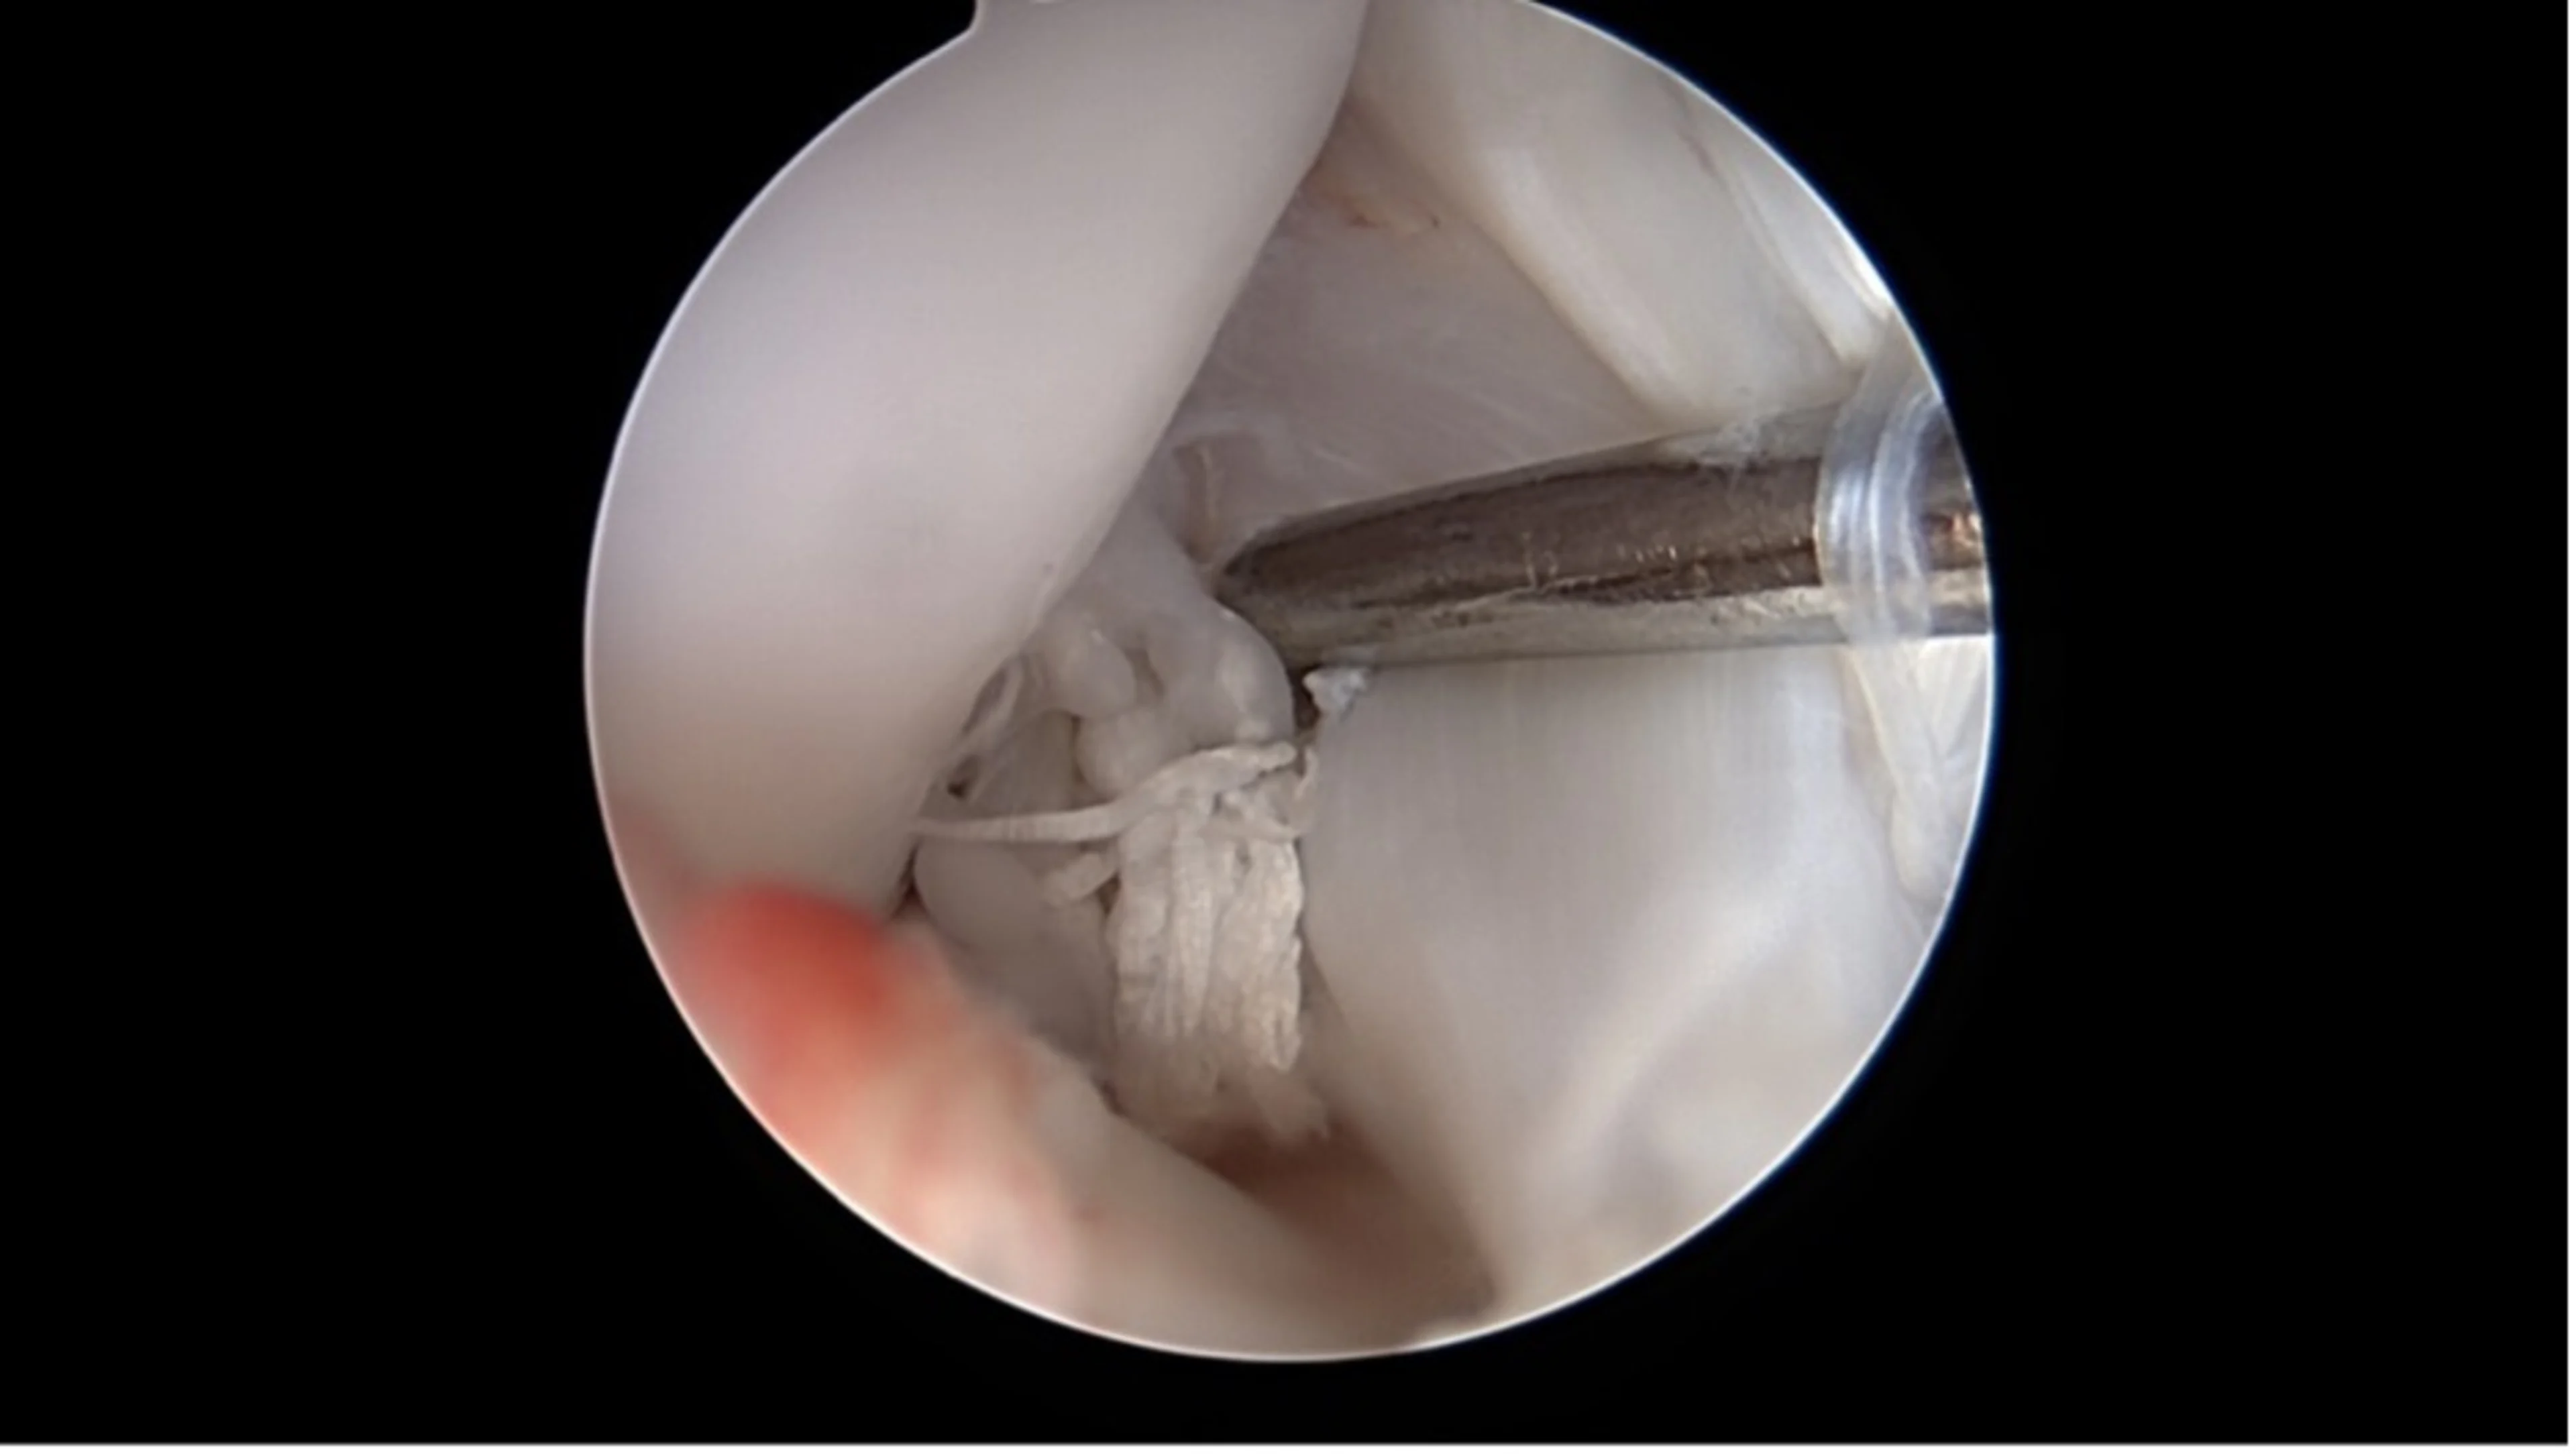

Une caméra miniaturisée permet de visualiser directement l’intérieur de l’articulation par de petites incisions cutanées. Les lésions du ligament croisé et les dommages associés comme les déchirures du ménisque peuvent être diagnostiqués et souvent traités immédiatement.

Rupture méniscale en anse de panier